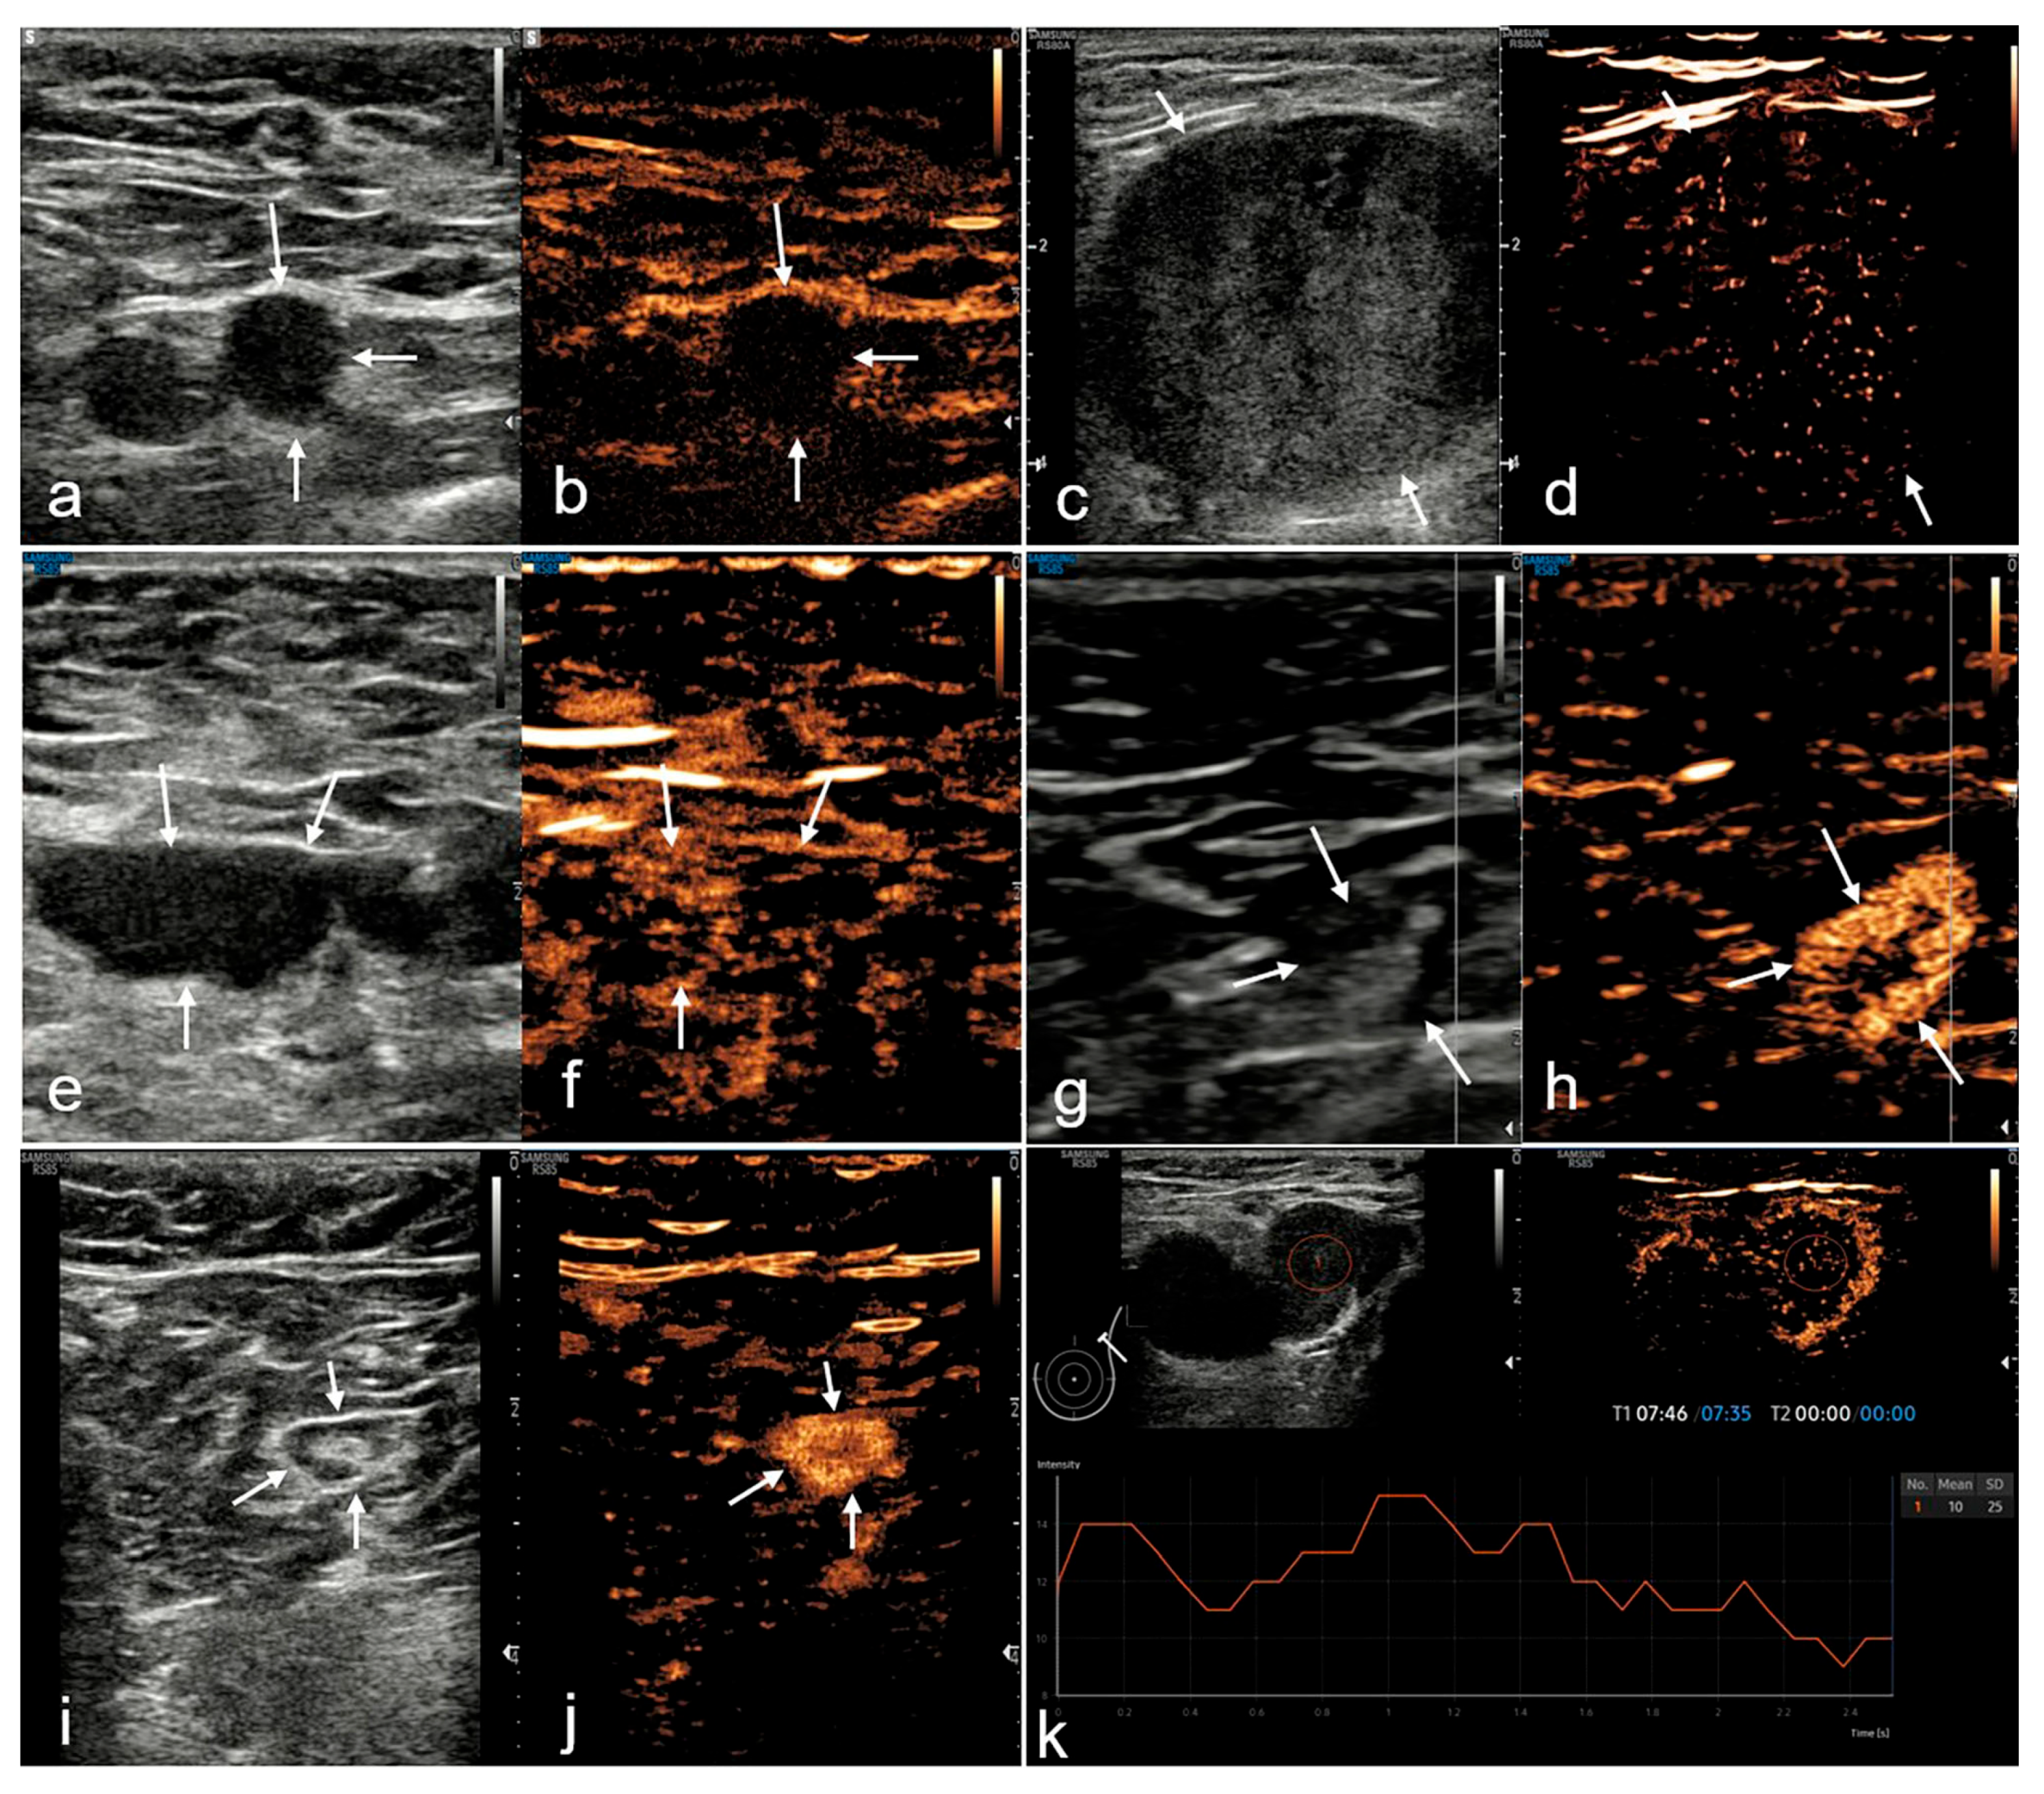

| The vascular phase | Intravenous | Sonazoid | 0–1 min | Enhancement homogeneity; perfusion defects; perfusion pattern |

| The postvascular phase | Intravenous | Sonazoid | 7–9 min | Enhancement degree; enhancement pattern; mean postvascular phase intensity |

| The postvascular phase | ||||

| Degree of enhancement | 58.04 | <0.001 *** | ||

| Relative hypo-enhancement | 64 (96.97%) | 6 (20.00%) | ||

| Relative hyper-enhancement | 2 (3.03%) | 24 (80.00%) | ||

| Patterns of enhancement | ||||

| Pattern I | 20 (30.30%) | 0 | ||

| Pattern II | 28 (42.42%) | 4 (13.33%) | ||

| Pattern III | 16 (24.24%) | 2 (6.67%) | ||

| Pattern IV | 0 | 6 (20.00%) | ||

| Pattern V | 2 (3.03%) | 18 (60.00%) | ||

| MPI, dB a | 12 (5, 20) | 75 (47, 93) | 97.50 c | <0.001 *** |